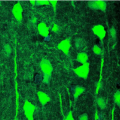

Quand les virus aident à mieux comprendre le fonctionnement du cerveau

Vie et Terre